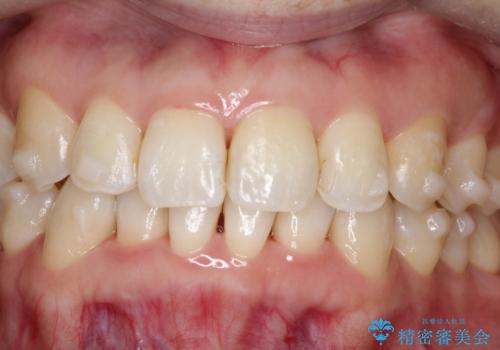

[エアフロー] スプレーの噴射によりしつこい色素沈着やプラークを除去

![[エアフロー] スプレーの噴射によりしつこい色素沈着やプラークを除去の症例 治療後](https://seimitsushinbi.jp/wp/wp-content/uploads/2021/11/IMG_0004-500x350.jpg?v=1636593307)